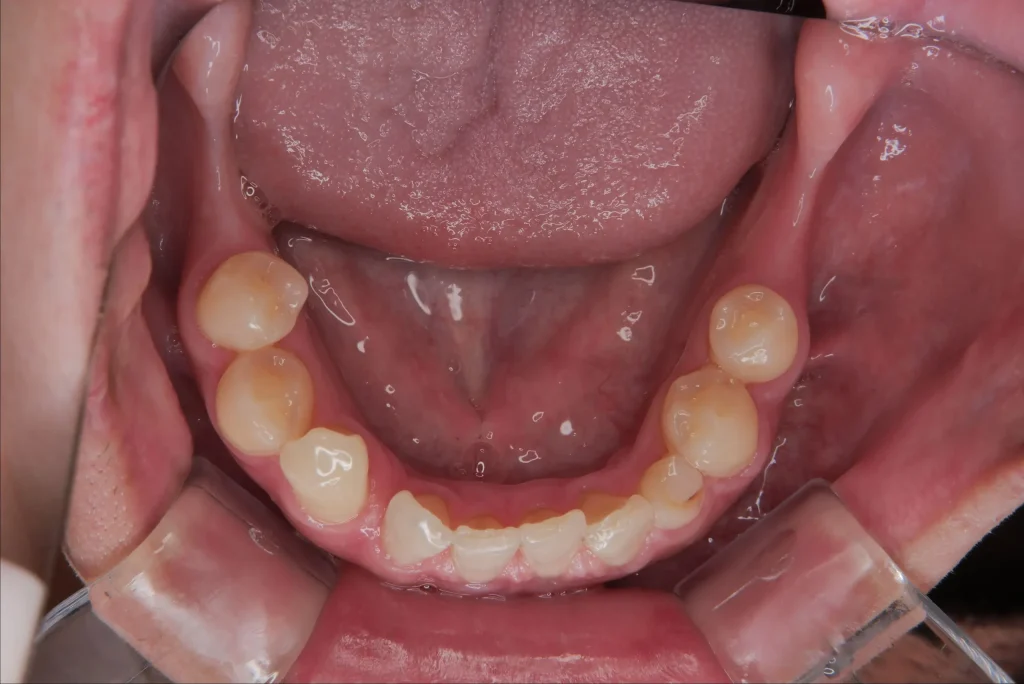

顎の骨が痩せてしまう

歯がある部分の骨は、噛む力によって維持されています。

歯がなくなるとその部分に刺激がなくなり、顎の骨が徐々に痩せていきます。

骨が減ると

- 将来インプラントが難しくなる

- 入れ歯が安定しにくい

といった問題が起こることがあります。